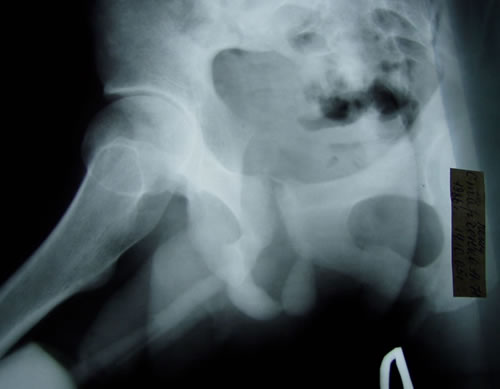

Рентгенография:

1. Восходящая цистография: